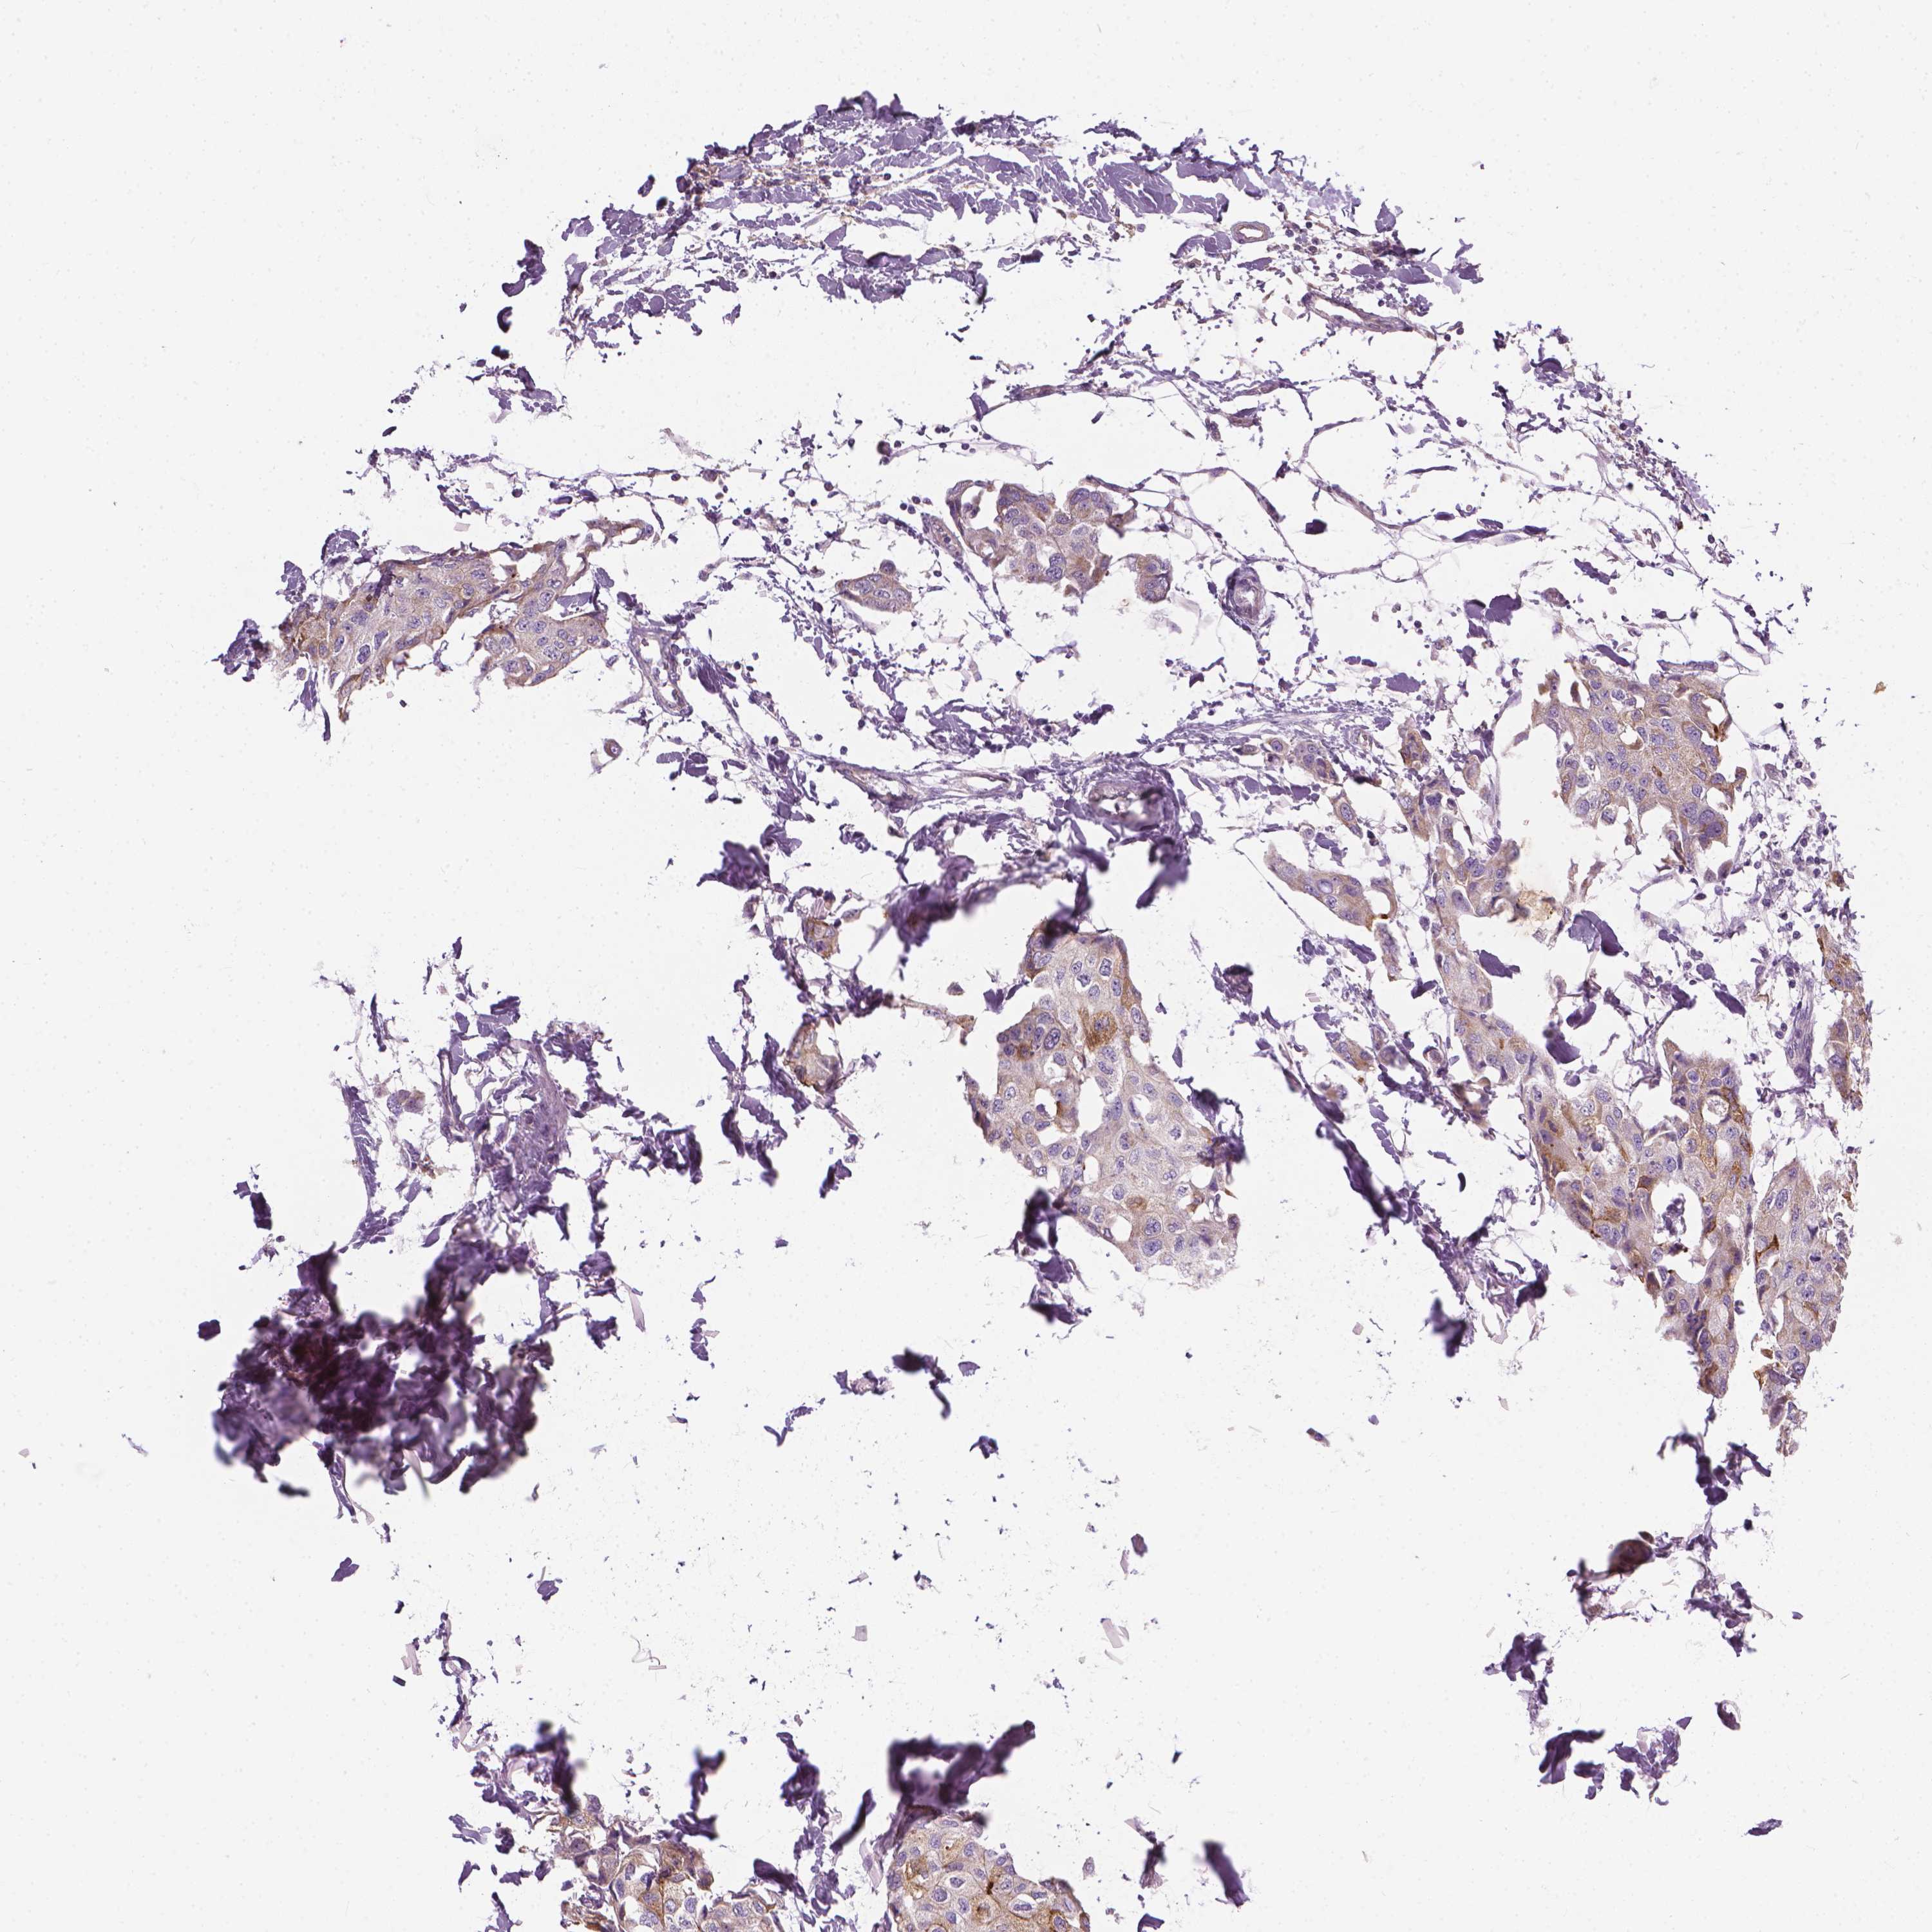

CANCER BREAST CANCER Show tissue menu

BRCA TCGA BRCA VALIDATION PROTEIN EXPRESSION